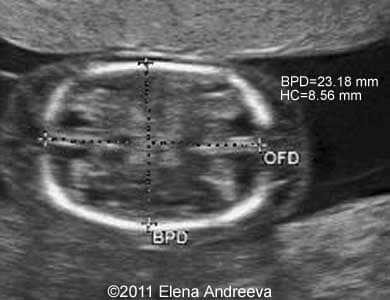

рџ ѓ Conjoined Twins Manila: filipino conjoined twins, klea ann and maurice ann misa, had been successfully separated after a complex 13 hour surgery sponsored by the saudi arabian government on thursday (april 23. Saudi arabia launched its 70th conjoined twins separation surgery in riyadh, beginning a 24 hour operation on filipino twins joined at the head. Saudi arabia’s expert team separates filipino conjoined twins after an 18.5 hour surgery at king abdullah specialist children’s hospital. The medical and surgical team of the saudi conjoined twins program began on thursday the separation surgery for the filipino conjoined twins klea and maurice ann, who are joined at the head, at king abdullah specialist children’s hospital in king abdulaziz medical city in riyadh. the surgery is in implementation of the directives of custodian of the two holy mosques king salman bin abdulaziz. A super complex surgery to separate filipino conjoined twins has started at the king abdullah specialist children's hospital in riyadh. doctors say there's a 50% risk because the girls are joined at the head and share veins in their brains. Conjoined twins refers to twins that are physically fused in utero and consequently at birth. this type of pregnancy is a complicated phenomenon that requires an interprofessional team approach to manage it effectively.

рџ ѓ Conjoined Twins Saudi arabia’s expert team separates filipino conjoined twins after an 18.5 hour surgery at king abdullah specialist children’s hospital. The medical and surgical team of the saudi conjoined twins program began on thursday the separation surgery for the filipino conjoined twins klea and maurice ann, who are joined at the head, at king abdullah specialist children’s hospital in king abdulaziz medical city in riyadh. the surgery is in implementation of the directives of custodian of the two holy mosques king salman bin abdulaziz. A super complex surgery to separate filipino conjoined twins has started at the king abdullah specialist children's hospital in riyadh. doctors say there's a 50% risk because the girls are joined at the head and share veins in their brains. Conjoined twins refers to twins that are physically fused in utero and consequently at birth. this type of pregnancy is a complicated phenomenon that requires an interprofessional team approach to manage it effectively.

Conjoined Twins Pacs A super complex surgery to separate filipino conjoined twins has started at the king abdullah specialist children's hospital in riyadh. doctors say there's a 50% risk because the girls are joined at the head and share veins in their brains. Conjoined twins refers to twins that are physically fused in utero and consequently at birth. this type of pregnancy is a complicated phenomenon that requires an interprofessional team approach to manage it effectively.